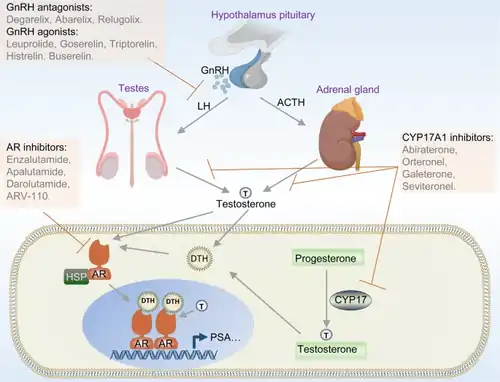

The prostate glands require male hormones, known as androgens, to work properly. Androgens include testosterone, which is made in the testes; dehydroepiandrosterone, made in the adrenal glands; and dihydrotestosterone, which is converted from testosterone within the prostate itself. Androgens are also responsible for secondary sex characteristics such as facial hair and increased muscle mass.

In 1941, Charles B. Huggins published studies in which he used estrogen to oppose testosterone production in men with metastatic prostate cancer. This discovery of "chemical castration" won Huggins the 1966 Nobel Prize in Physiology or Medicine.[200] The role of the gonadotropin-releasing hormone (GnRH) in reproduction was determined by Andrzej W. Schally and Roger Guillemin, who both won the 1977 Nobel Prize in Physiology or Medicine for this work. GnRH receptor agonists, such as leuprorelin and goserelin, were subsequently developed and used to treat prostate cancer.[201][202]

All medications for CRPC block AR signaling via direct or indirect targeting of the AR ligand binding domain (LBD). Over the last decade molecules that could successfully target these alternative domains have emerged.[217] Such therapies could provide an advantage; particularly in treating prostate cancers that are resistant to current therapies like enzalutamide.[217]

Cancer models

Scientists have established a few prostate cancer cell lines to investigate the mechanism involved in the progression of prostate cancer. LNCaP, PC-3 (PC3), and DU-145 (DU145) are commonly used prostate cancer cell lines. The LNCaP cancer cell line was established from a human lymph node metastatic lesion of prostatic adenocarcinoma. PC-3 and DU-145 cells were established from human prostatic adenocarcinoma metastatic to bone and to brain, respectively. LNCaP cells express androgen receptor (AR), but PC-3 and DU-145 cells express very little or no AR. AR, an androgen-activated transcription factor, belongs to the steroid nuclear receptor family. Development of the prostate is dependent on androgen signaling mediated through AR, and AR is also important during the development of prostate cancer.

The proliferation of LNCaP cells is androgen-dependent but the proliferation of PC-3 and DU-145 cells is androgen-insensitive. Elevation of AR expression is often observed in advanced prostate tumors in patients.[226][227] Some androgen-independent LNCaP sublines have been developed from the ATCC androgen-dependent LNCaP cells after androgen deprivation for study of prostate cancer progression. These androgen-independent LNCaP cells have elevated AR expression and express prostate specific antigen upon androgen treatment. The paradox is that androgens inhibit the proliferation of these androgen-independent prostate cancer cells.[228][229][230]